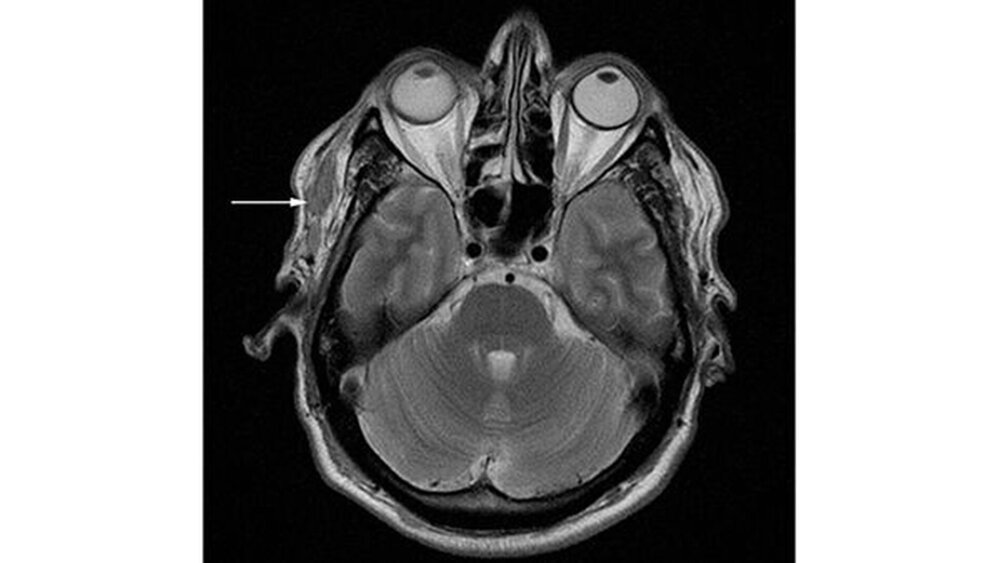

Korrespondierend zum klinischen und sonografischen Befund zeigte sich in einer von extern bereits vorliegenden MRT-Untersuchung eine unscharf begrenzte, inhomogene Raumforderung (Abbildungen 4 und 5). Über einen präaurikulären Zugang wurde der Befund scharf aus dem umliegenden Gewebe unter Schonung der relevanten Gefäß- und Nervstrukturen entfernt (Abbildung 6).